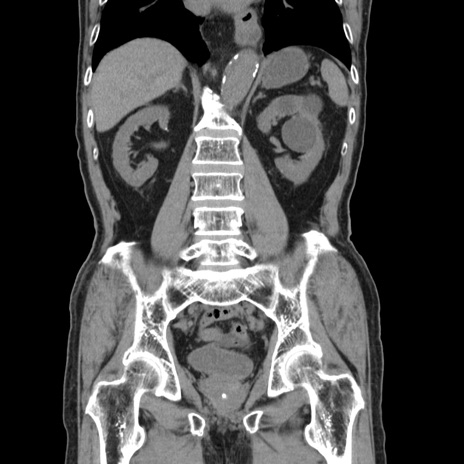

症例24(冠状断像)

【症例】80歳代男性

【主訴】左側腹部痛、嘔吐

【現病歴】本日早朝より左腹部に痛みあり。昼頃嘔吐認めたため、救急要請。

【既往歴】直腸癌(Mile手術)、胆摘

【身体所見】意識清明、BT 35.9℃、BP 221/93mmHg、SpO2 97%(RA) 、腹部:左ストーマ周囲に限局性の腹部膨隆あり。 膨隆部自発痛・圧痛あり・軟。

【データ】WBC 7700、CRP 0.09